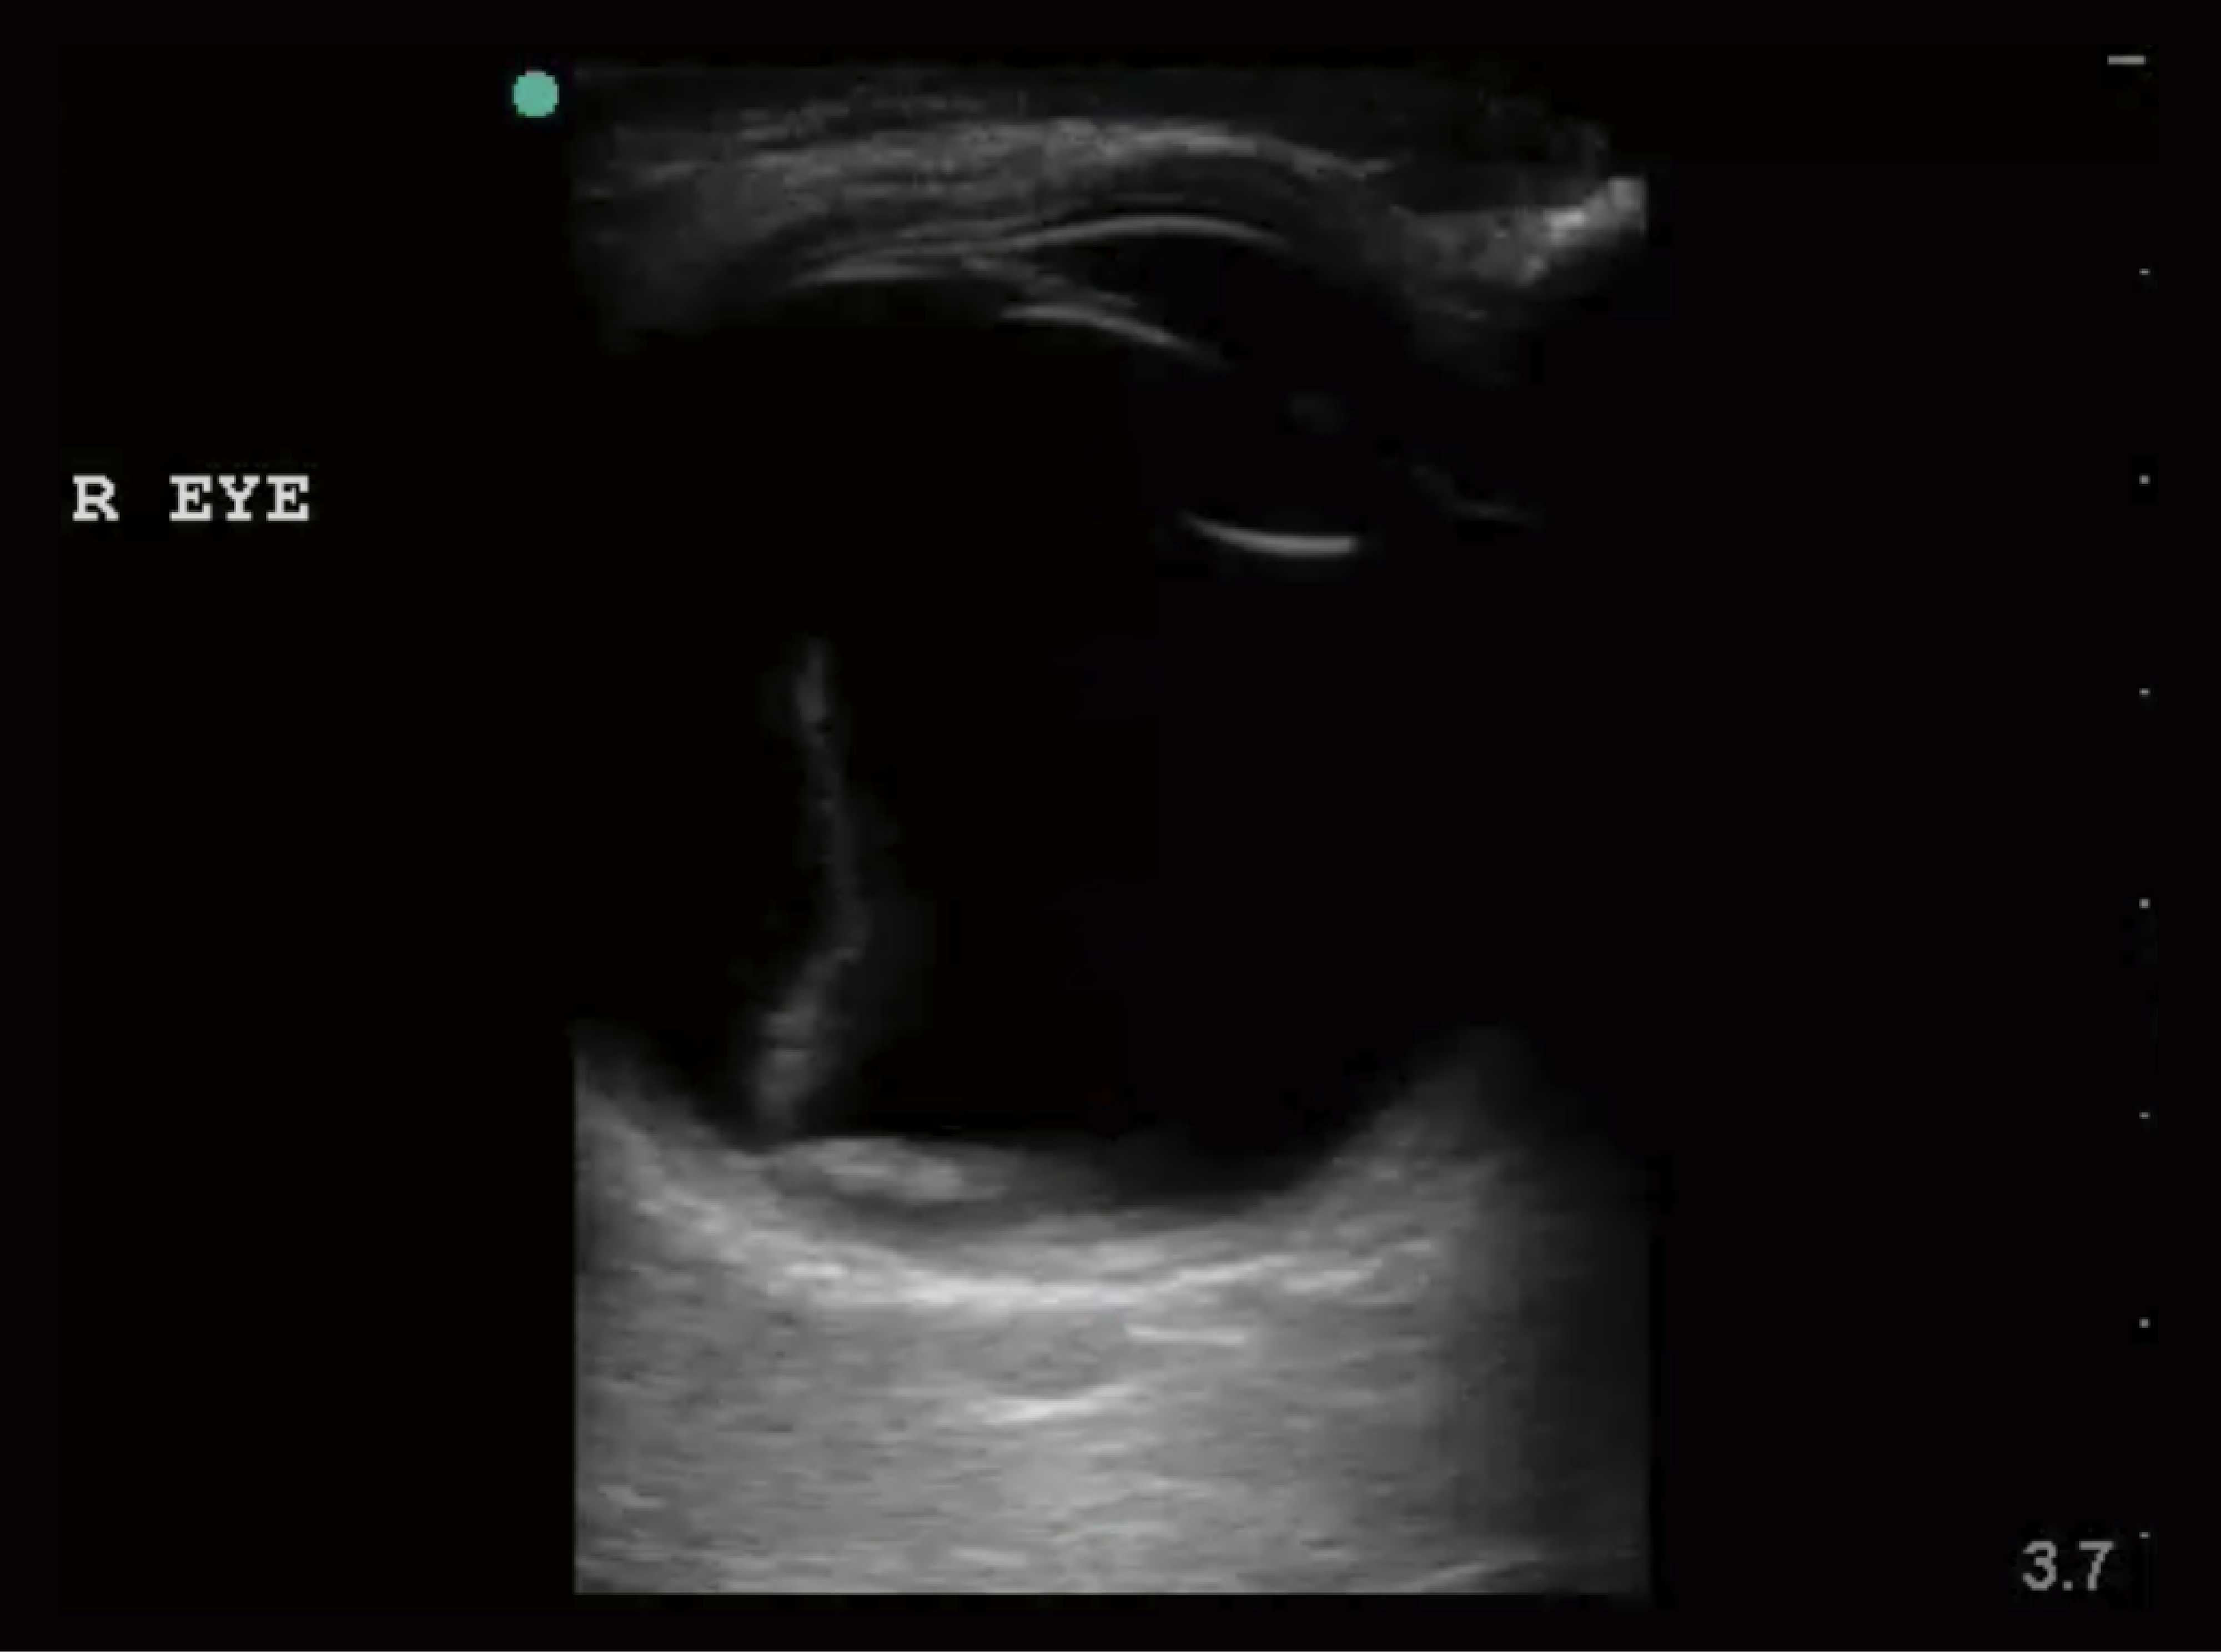

77-year-old man presents with vision loss. He reports seeing flashes of light and then losing vision gradually. Denies pain. Visual acuity is 20/200 in the affected eye. Bedside ultrasound image shown below. What is the diagnosis?

Retinal detachement

Be aware of Mac on vs Mac off (the macula is located on temporal side relative to optic disc).. Mac on is emergent